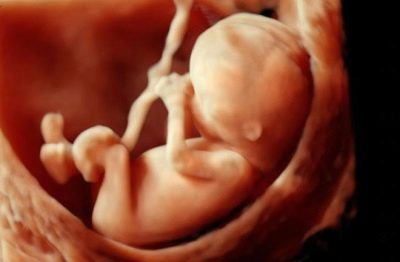

Что же происходит с эмбрионом на 14 неделе беременности? Как он выглядит и как развивается?

- Представьте себе небольшое яблоко. Примерно таким по размеру является плод на этом сроке. Его вес сейчас увеличился до 25 грамм. Будущий малыш подрос примерно до 80-113 мм.

- Очень сильно меняется внешний вид плода. Личико становится более круглым. Вырисовываются щечки. Лобик и носик выступают вперед. На голов появляется волосистый покров.

- Будущий ребеночек начинает все активнее шевелиться в те периоды, когда не спит в мамином животике. Малыш активно толкается изнутри ручками и ножками, хотя еще силенок маловато, и эти пинки на 14 неделе еще трудно почувствовать

- Дыхательная система плода активно развивается. Малыш даже совершает подобие дыхательных движений. Диафрагма двигается так, как будто при дыхании. Это своего рода тренировка перед тем, как ребенок в первый раз сделает вдох.

- Ротик малыша (голосовая щель) начинает приоткрываться. Эмбрион как будто шевелит губами и может заглатывать околоплодные воды.

- Продолжается формирование половых органов. Хотя даже сейчас еще трудно определить на УЗИ пол будущего ребенка. У эмбрионов женского пола яичники опускаются в область таза, а у особей мужского поля формируется простата.

Будущий малыш не только довольно хорошо видит и слышит, но уже может выпрямлять шею, корчить рожицы, зевает или сосет пальчик.

Сейчас ваш малыш весит около 50 г, его рост – около 12 см, размер головы – 3 см, длина бедра – 16 мм, окружность грудной клетки – 26 мм. Глаза пока плотно сжаты, но зрительные нервы уже сформированы. Сердце бьется с частотой 120-160 ударов в минуту. Он уже умеет мочиться и распознавать вкус. То, что вы едите, меняет консистенцию околоплодных вод, а малыш реагирует на сладкое, горькое и кислое различными гримасами. Состояние вашего малыша очень зависит от вашего самочувствия. Если вы взволнованы, расстроены, его сердечко начинает биться быстрее, а движения становятся совершенно хаотичными.